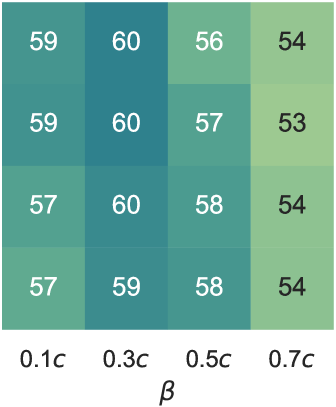

We performed an ablation study on the parameters and in our reward function. These parameters correspond to the late visit and true dismissal actions, respectively. Our experiment involved an evaluation on a grid, where and .

Given that the reward scale fluctuates with adjustments to these parameters, as indicated in Equations 13 and 12, we introduced the normalized score – recall-over-cost ratio as a metric for assessment of the results. For a comprehensive evaluation of accuracy, we utilized the BA score. The results are illustrated in Figure 7. Our findings revealed that the optimal parameter combination was and . This combination yielded a BA score of and a recall-over-cost ratio of , the highest scores among other combinations.